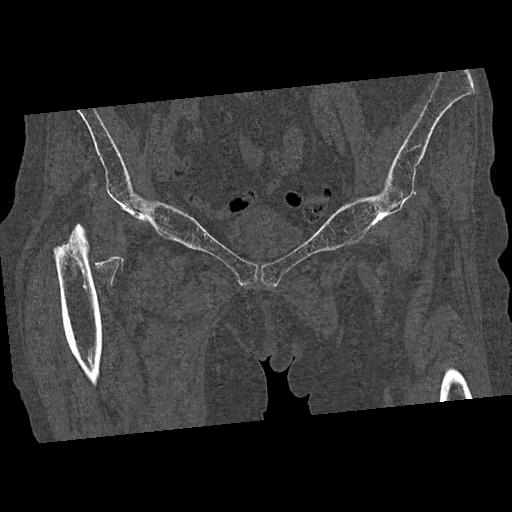

100703 1/27 両股正面+軸 1/29 両股正面+軸 94歳女性 パンソンロン